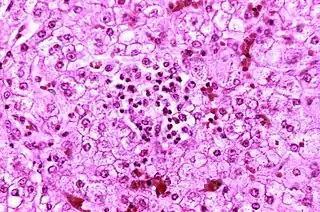

![]() Histopatología de un hígado autópsico procedente de un niño que murió de síndrome de Reye. Los hepatocitos se tiñen pálidamente debido a las gotitas intracelulares de grasa. | ||

El síndrome de Reye es una enfermedad pediátrica grave que suele producirse con mayor frecuencia en niños menores de 10 años. Se caracteriza por encefalopatía no específica de progresión rápida,[1] con degeneración adiposa de las vísceras y alteración del metabolismo. Afecta principalmente al hígado y cerebro.

Es una esteatosis hepática microvesicular. El sistema nervioso central aparece edematoso.

Al microscopio electrónico se ven unas mitocondrias anormales. La causa de la enfermedad es un trastorno mitocondrial sistémico que impide la β-oxidación de los ácidos grasos.